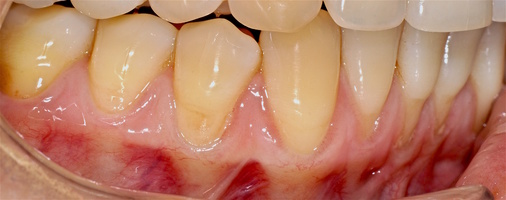

1. Генерализованные рецессии в области нижней челюсти оперировались в один этап все 12 зубов, фронтальный участок с аутотрансплантатом от 3.2 до 4.2 зубов. А дистальные участки от 3.6 до 3.3 и от 4.6 до 4.3 зубов с использованием пластического материала ТМО (dura mater) (рис. 4а-з).

Участки 3.3-3.6 зубов и 4.3-4.6 зубов были проопери- рованы зеркально по методу коронально-ротированно- го лоскута по M. De Sanctis и G. Zucchelli (2000) с одним послабляющим вертикальным разрезом в области 3.3 зуба или 4.3 зуба.

Второй сегмент был прооперирован через 4 месяца после операций на нижней челюсти, область операции включила в себя зубы от 2.1 до 2.6.

В области 2.3 зуба глубина рецессии составила 6 мм (2-й класс по Миллеру), кератинизированная десна отсутствует, толщина слизистой — 0,7 мм. Это показание к применению аутотрансплантата(свободного десневого деэпителизированного трансплантата) именно в области 2.3 зуба. Донорская зона позволила сделать забор аутотрансплантата размером 15 мм, которого хватило на общую ширину рецессий двух зубов: 2.3 и 2.4.

При устранении рецессий десны коронально-смещенным лоскутом по De Sanctis M. и Zucchelli G. в остальных участках был использован пластический материал аллогенного происхождения — ТМО (dura mater).